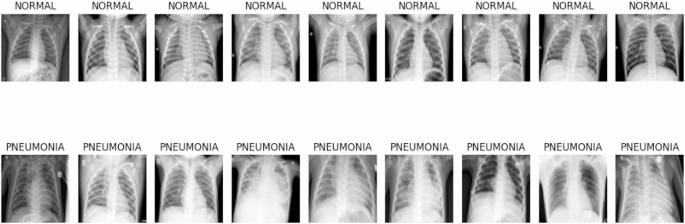

Figure 1 displays illustrative chest radiographs contrasting healthy lung scans with those affected by pneumonia. The normal images feature uniformly dark lung regions, sharply defined diaphragmatic contours, and visible vascular markings. In contrast, the pneumonia cases exhibit localized to widespread white patches that blur anatomical landmarks—such as costophrenic angles and heart borders—indicating areas of alveolar consolidation and increased tissue density. These visual distinctions underscore the image characteristics that the hybrid SNN-GRU network must learn to differentiate.

Different classes in pneumonia chest X-ray dataset.